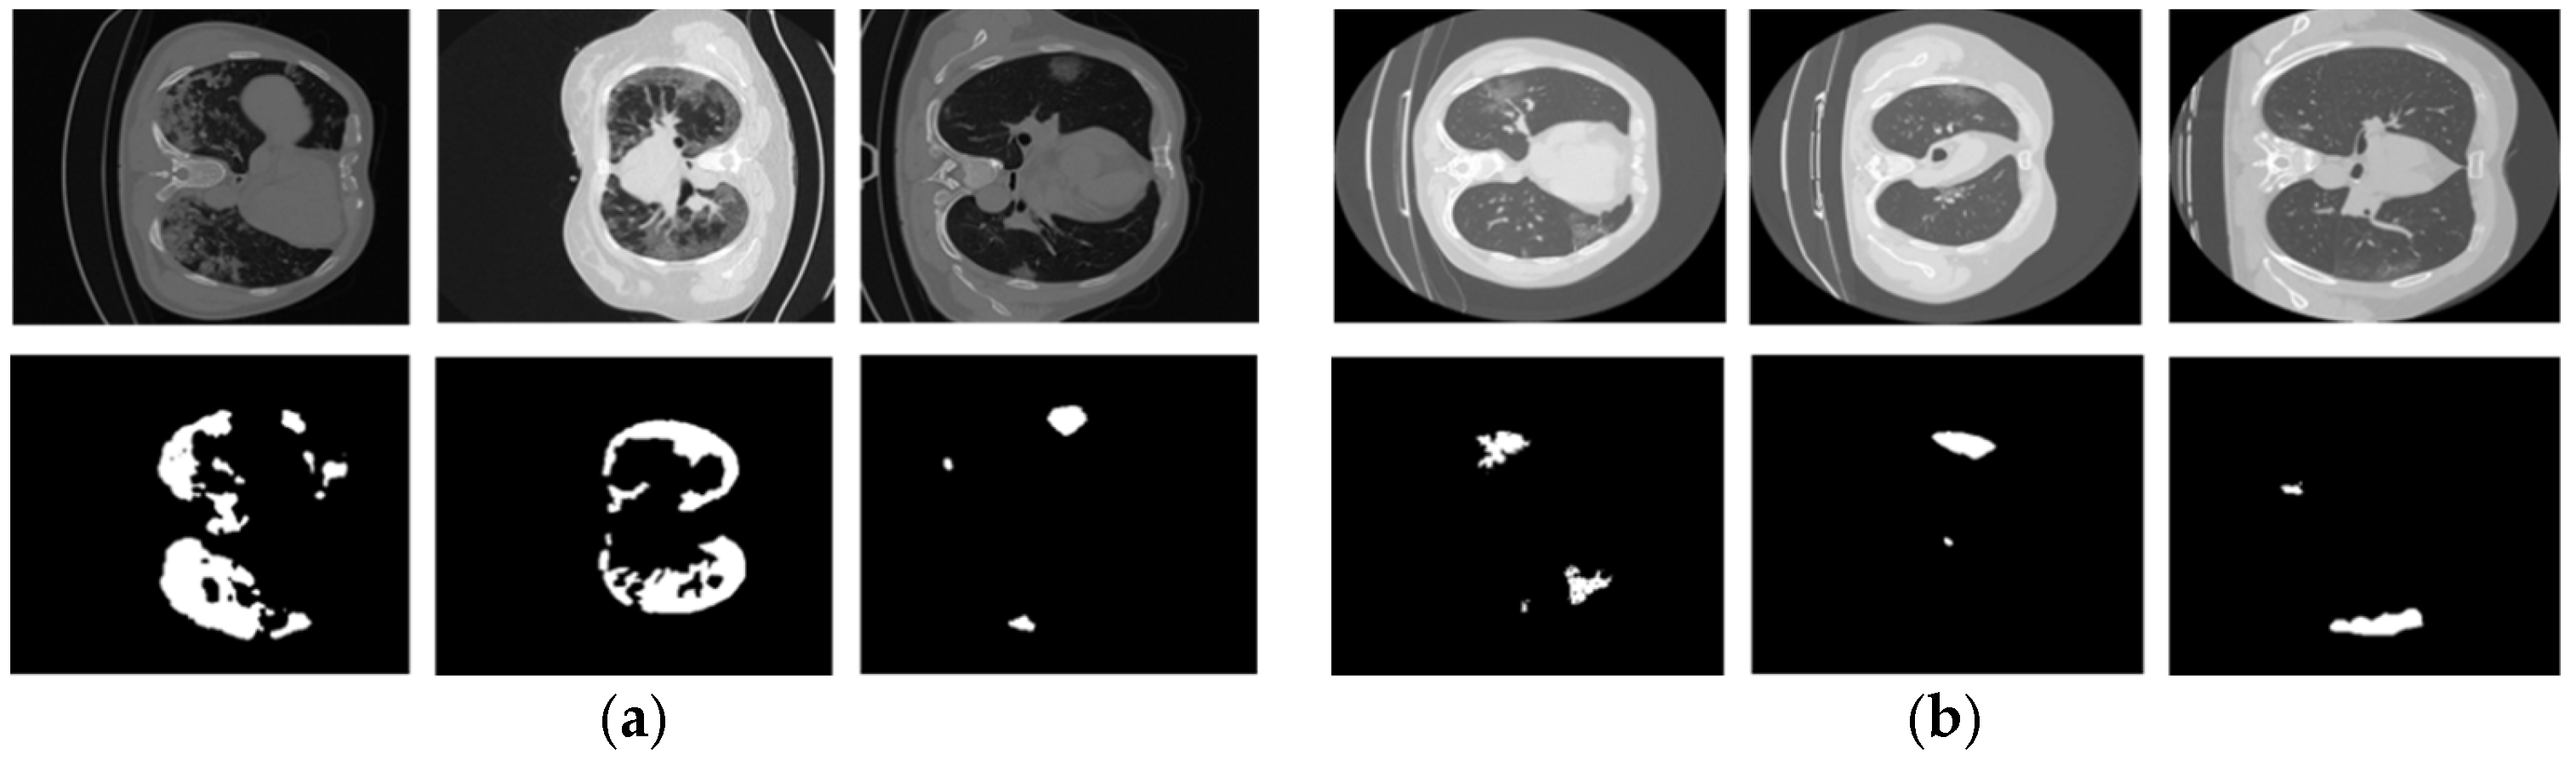

2.1. Datasets